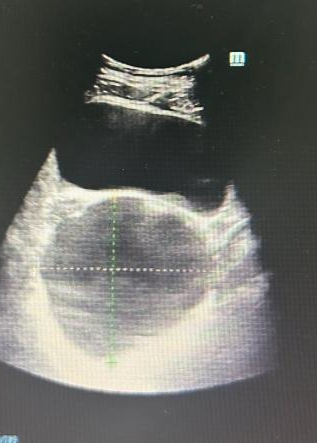

妇科彩超提示盆腔囊性占位

手术顺利开展。术中,任医生在患者右侧卵巢发现一枚约10cm×10cm×9cm的囊实性肿瘤(术后病理确诊为成熟性畸胎瘤),为最大限度保护卵巢功能,团队全程采用钝性分离手法,避免使用电凝器械,每一步操作都精准而轻柔。凭借娴熟的腹腔镜技术,手术过程顺利,出血极少,圆满实现了“微创治疗”与“功能保护”的双重目标。